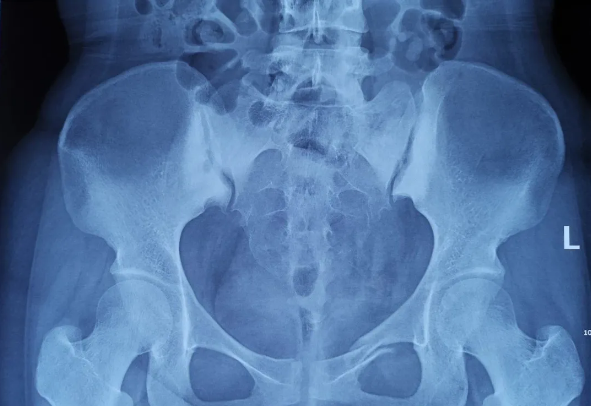

由北京積水潭醫院院長蔣協遠、智能骨科研究型病房主任王軍強帶領的智能骨科團隊,運用骨科機器人輔助經皮骨盆通道螺釘置入技術,成功救治了一名90歲高齡的骨盆骨折患者。 -

近日,天璣?骨科手術機器人落戶南昌市第一醫院,助力骨盆骨折閉合復位內固定術順利完成。作為江西省首先采用5G引導下的骨科機器人手術,天璣?骨科手術機器人用它的“透視眼”,以三維影像掃描進行深層三維空間精準定位,為患者“量身定做”了最理想、最安全的教科書般通道,完成了復雜骨盆骨折微創治療一次性完美置釘及腰椎骨折微創經皮置釘的首秀,成為江西省骨科發展的標志性事件,同時也是江西省骨科步入新型數字智慧骨科時代的重要里程碑事件。 -